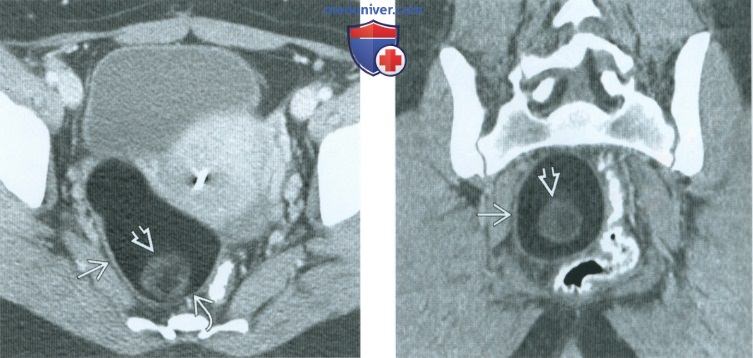

КТ диагностика тубоовариального абсцесса: Подходы и изображения

Раздел: Объективный взгляд